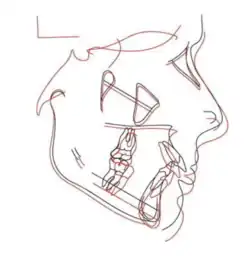

In Angle's classification system for malocclusion, a Class II bite (Figure 1) occurs when the lower jaw (mandible) is positioned more behind relative to the upper jaw (maxilla). This misalignment means that when the teeth come together, the lower teeth bite significantly behind the upper teeth[2] creating a large horizontal gap between upper and lower teeth. It is defined as increased overjet, which is measured from the labial surface of the tips of the upper incisors to the labial surface of the lower incisors horizontally.[3]

The size of the condyle, distance between the two condyles, and the length of the mandible increased. The twin block appliance enabled the growth of the condyle in a backwards and upwards direction. Based on cephalometric analysis, as given in Figure 21, the angle of SNB (the position of the mandible to the base of the skull) increased, and the angle of SNA (the position of the maxilla to the base of the skull) and ANB (anteroposterior relationship between the maxilla and mandible) decreased thus reducing the Class II skeletal malocclusion.[24]